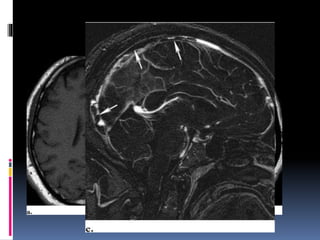

Axial FLAIR scan demonstrates typical findings of bilateral external (cortical)

watershed infarcts

Nearly symmetric confluent and punctate deep white matter hyperintensities

are seen above and behind the lateral ventricles .

FLAIR scan just above the previous image shows distinct bilateral rosary-like

white matter hyperintensities